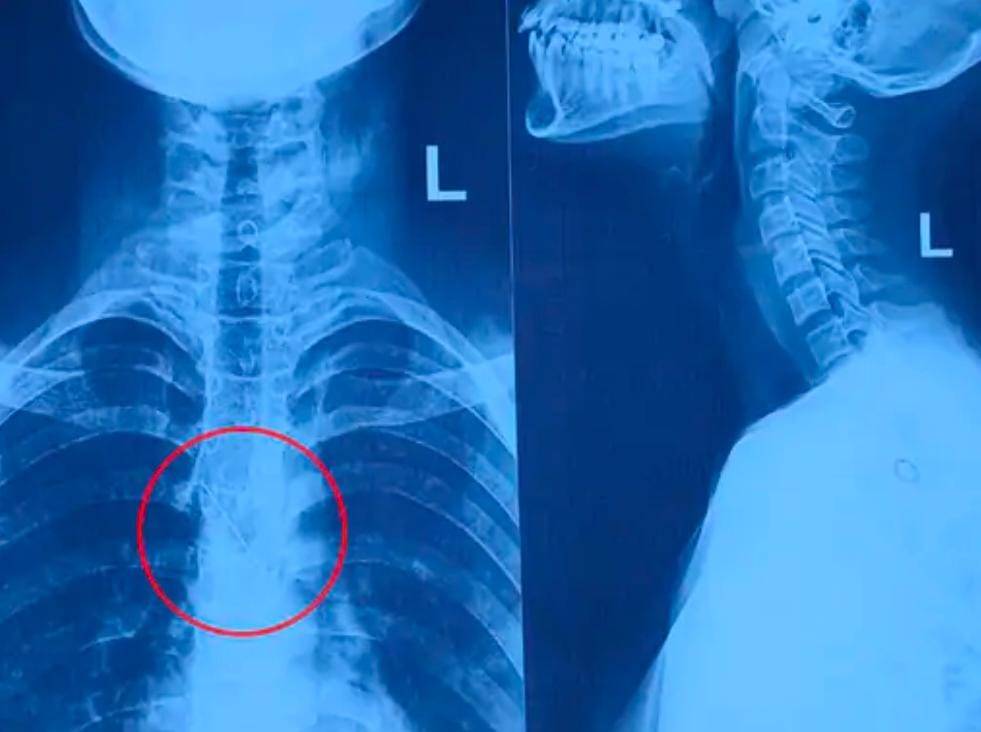

ઘટના બન્યાના માત્ર બે-ત્રણ કલાકમાં જ કિશોરીને સયાજી હોસ્પિટલમાં લાવવામાં આવી હતી. તપાસ દરમિયાન કરાયેલા એક્સ-રેમાં ખુલ્યું કે પિન શ્વાસનળીના વિભાજન ભાગ પાસે ડાબી બાજુના નીચેના ફેફસાંમાં અટવાઈ ગઈ હતી. પરિસ્થિતિની ગંભીરતા જોતા તાત્કાલિક એનેસ્થેશિયા નિષ્ણાતની મદદથી કિશોરીને ઓપરેશન થિયેટરમાં લઈ જવામાં આવી.

ENT વિભાગના નિષ્ણાંત ડૉ. રાહુલ ગુપ્તાની ટીમે બ્રોન્કોસ્કોપી પદ્ધતિ દ્વારા લગભગ 45 મિનિટથી એક કલાકની જટિલ સર્જરી કરી, કોઈ ચીરો પાડ્યા વગર પિન સફળતાપૂર્વક બહાર કાઢી હતી. ડૉ. ગુપ્તાએ જણાવ્યું કે પિન ગળા પરથી ફેફસાં સુધી ઘણી અંદર સુધી પહોંચી ગઈ હતી અને કાઢતી વખતે તે થોડી વળી પણ ગઈ હતી, જેના કારણે પ્રક્રિયા મુશ્કેલ બની હતી.

બે દિવસ સુધી એન્ટિબાયોટિક ઈન્જેક્શન અને પોસ્ટ-ઓપરેટિવ ચેસ્ટ એક્સ-રે બાદ કિશોરીને સંપૂર્ણ સ્વસ્થ જાહેર કરી રજા આપવામાં આવી છે. ખાસ નોંધનીય બાબત એ છે કે આ સમગ્ર સારવાર અને સર્જરી સયાજી હોસ્પિટલમાં સંપૂર્ણ નિઃશુલ્ક કરવામાં આવી હતી, જ્યારે ખાનગી હોસ્પિટલમાં આ પ્રકારની સર્જરીનો અંદાજિત ખર્ચ ₹60,000 થી ₹70,000 સુધીનો થાય છે.